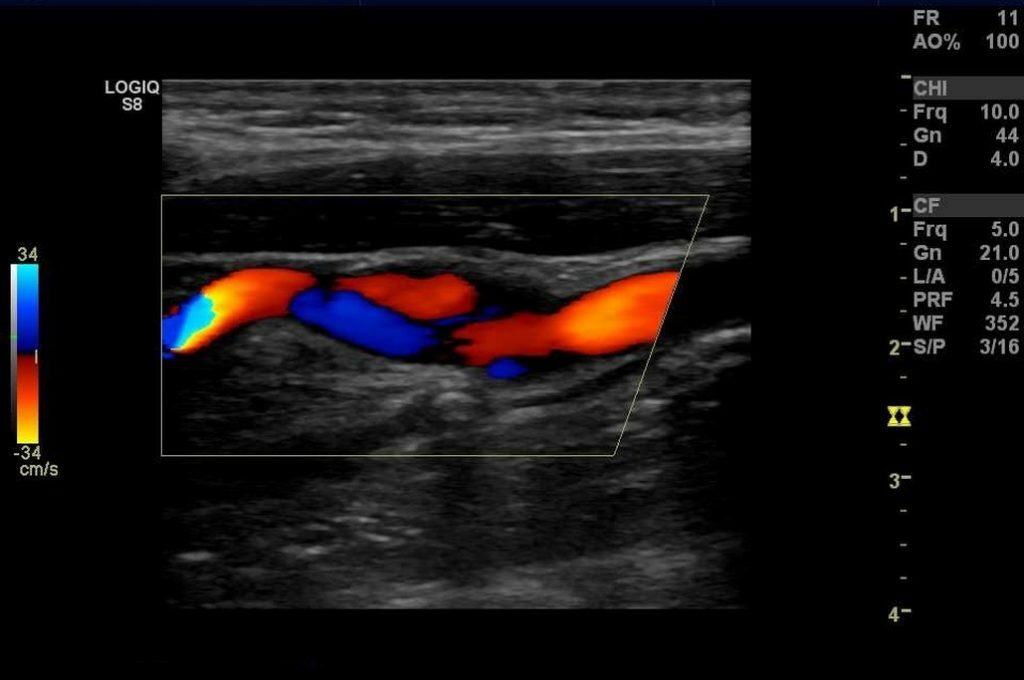

Исследование сосудов головы и шеи

Допплерография головы и шеи

Цветное дуплексное сканирование магистральных артерий головного мозга

Транскраниальное исследование сосудов головы